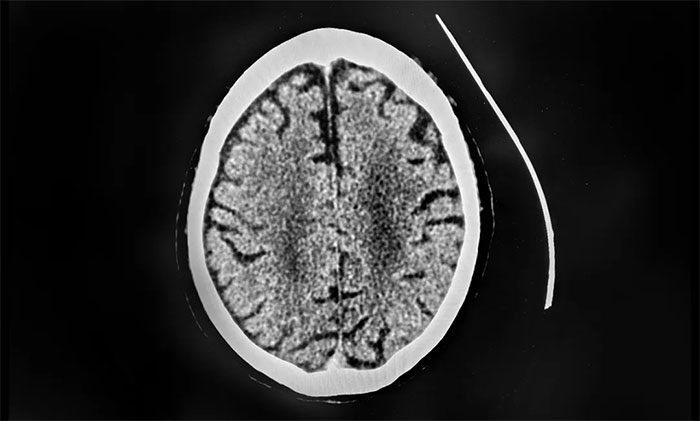

有着30多年丰富临床经验的上海蓝十字脑科医院学术副院长、4A脑血管病一科主任席刚明教授指出,患者从症状上看怀疑颅内静脉窦血栓形成。急查颅脑CT平扫未示新发出血,发现右侧横窦、窦汇、上矢状窦密度增高,此外,D-二聚体(检测血栓形成的关键指标)达到26.21mg/L,远超正常值。

▲ CT检查发现右侧横窦、窦汇、上矢状窦密度增高